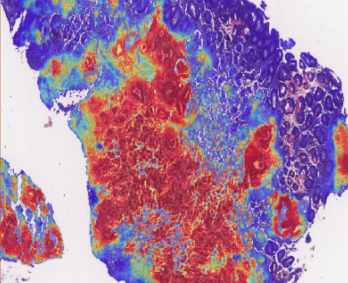

Block interception and precise amplification of gastric biopsy digital images; Tumor segmentation model

and heat map analysis; Feature extraction, negative and positive classification to predict tumor probability with high sensitivity.

2. Thermal analysis: show the risk level in each area, locate abnormal follicular cells and make an intelligent rank for quick review,

visualize each phase and one-click for online report.

3. WSI reasoning: WSI slide-window reasoning, intelligent zoom in, adenoma identification optimization.